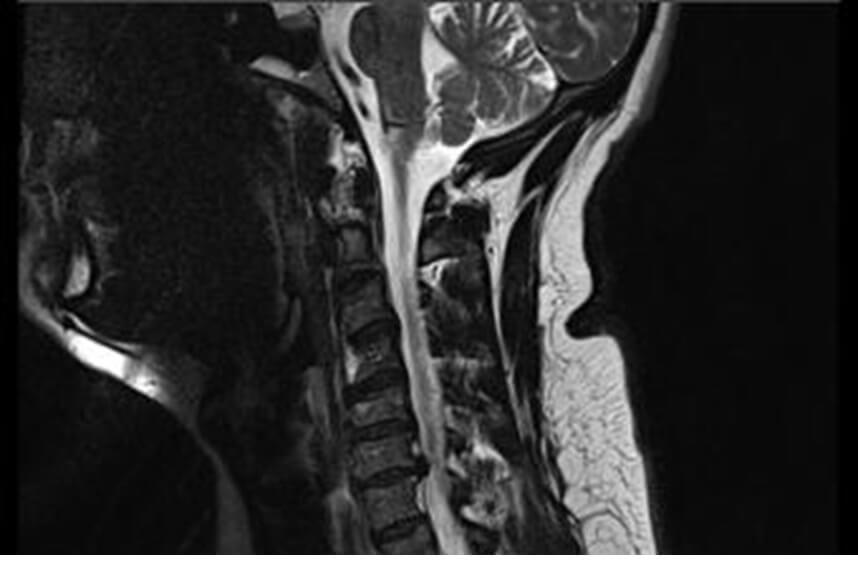

The clinical diagnosis can be made based on the path and intensity of the pain and can be confirmed by imaging through X-rays, MRI, or CT. In most cases, conservative treatment is recommended. In the initial stages, a cervical collar and medication for pain and inflammation management may be recommended. Manual therapy is recommended at the beginning of physical therapy sessions (osteopathy, therapeutic massage, mobilizations of the area, stretching), followed by therapeutic exercises to regain maximum range of motion. Maintenance programs are also very important to help patients maintain muscle strength, but poor postures that can worsen the condition of the affected discs should be avoided.

It is very important to have an accurate diagnosis to create a tailored physical therapy program. Spondylosis is highlighted radiologically, and MRI or CT can be used to see the impact of the problem on the spinal cord and cervical nerve roots.